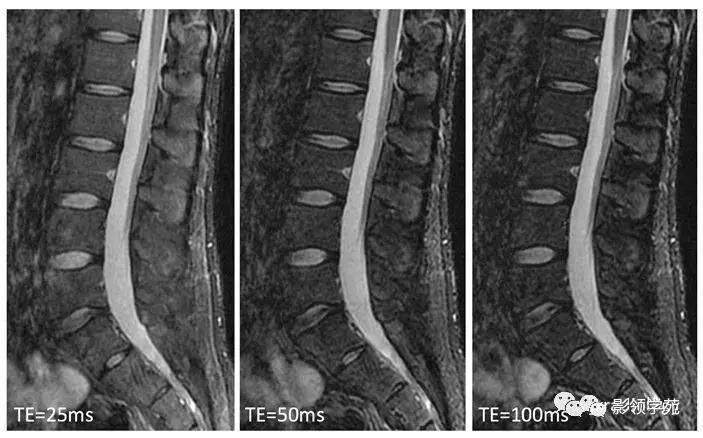

图1:20岁,健康男性。各种回波时间(TE)的STIR矢状面图像。3种不同TE的腰椎矢状面STIR图像在相同窗宽/窗位水平设置下。TE的设置会影响图像的对比度。当TE设定较长时,肌肉和皮下脂肪的信号强度相对较低。